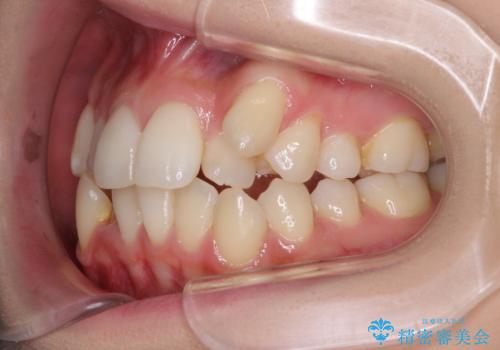

補助装置を併用したインビザラインでの八重歯の抜歯矯正

- 八重歯と奥歯の咬み合わせを気にして来院された患者様です。

インビザラインによる矯正治療を希望されたため、八重歯改善のための抜歯矯正部分は補助装置を併用し、その後はインビザラインにて行うこととしました。

下顎の右側変位が顕著であったため、ワイヤー矯正の方が咬み合わせは改善しやすいのですが、ある程度は時間がかかっても良いとのことであったので、インビザラインにて矯正治療を行うこととしました。

骨格的に下顎が右側に変位していたため、上下正中を合わせることは困難であることは分かっていました。それでも、なるべく合わせるようにとしたため、治療期間は長期間となりました。

長期間とはなりましたが、咬み合わせが改善され、患者様には大変満足していただきました。